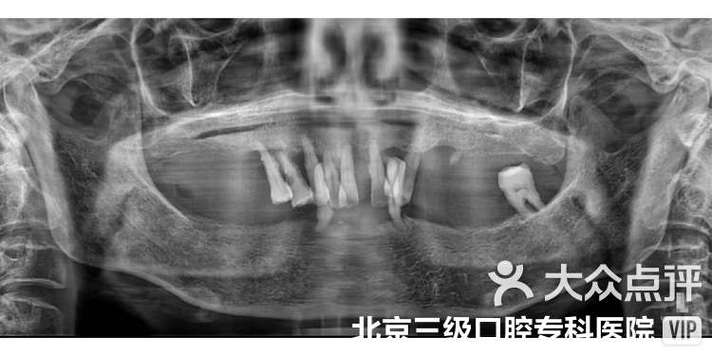

- 全面检查与评估: 口腔检查、CBCT(锥形束CT)评估骨量、骨质、重要神经血管位置、全身健康状况评估。